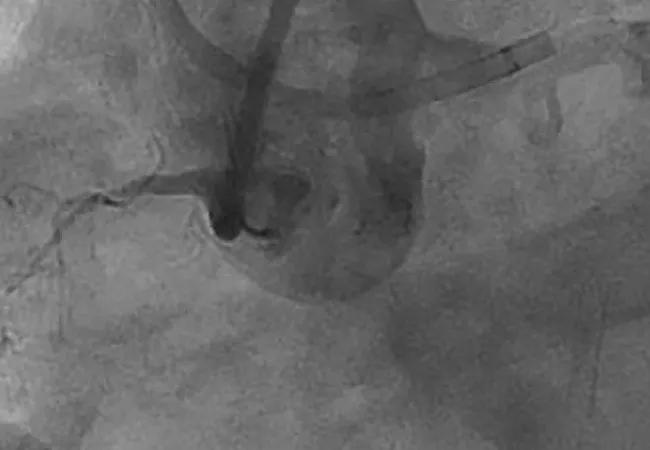

Coronary chronic total occlusions (CTOs) have been described as the last frontier of interventional cardiology. Despite the complexity of these lesions, recent years have seen rising rates of procedural success without offsetting compromises in safety.